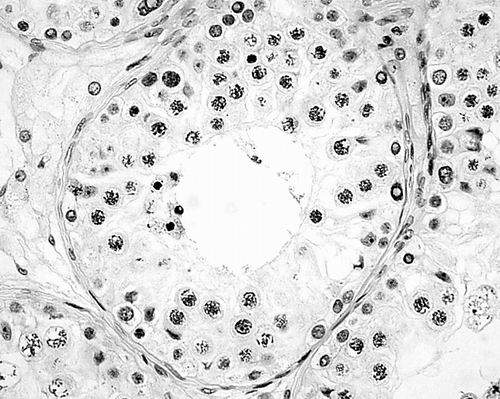

图为人类睾丸组织学图谱。A为精子发生正常的曲精小管;B为精母细胞发育停滞的曲精小管。